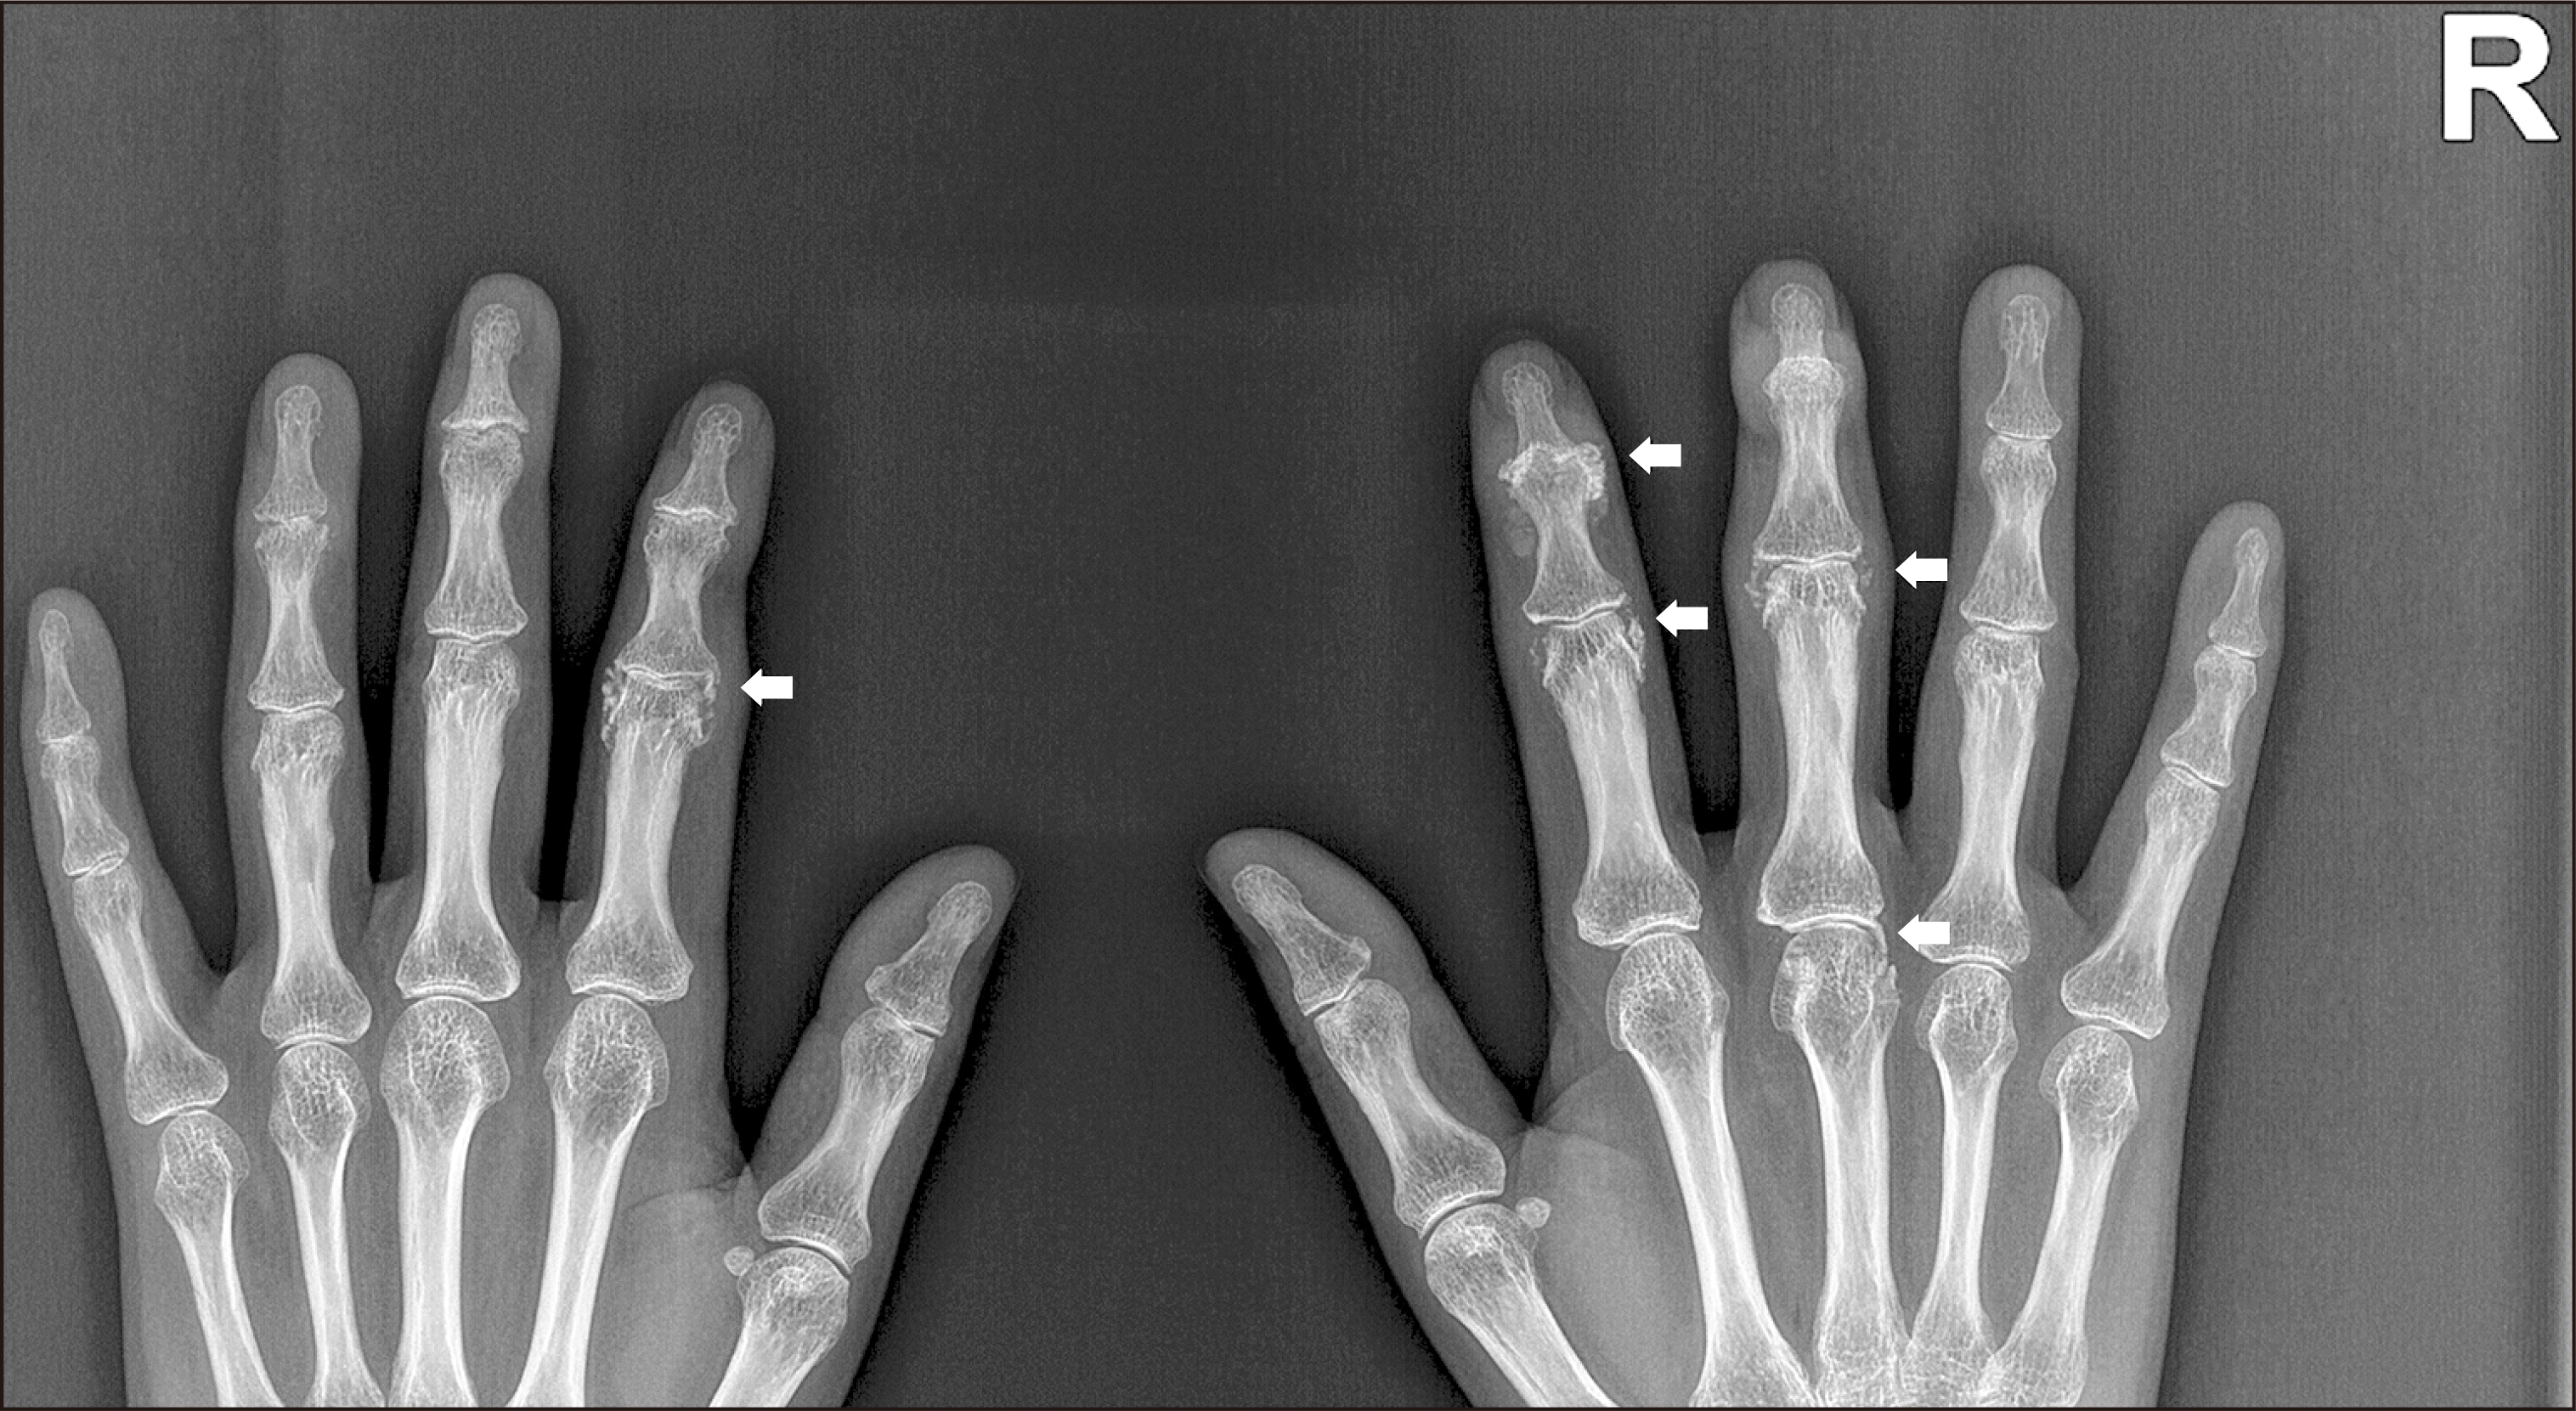

A 50-year-old woman presented with a 4-year history of intermittent swelling and progressive deformities of the hand joints. Serum rheumatoid factor and anti-citrullinated protein antibody tests showed negative results, and the C-reactive protein level was 0.11 mg/dL. Radiograph revealed joint space narrowing, erosions, and subchondral sclerosis involving several proximal interphalangeal (PIP) and distal interphalangeal (DIP) joints of both hands. Of note, we observed periarticular calcifications around the second DIP and PIP, third PIP, and third metacarpophalangeal (MCP) joints on the right and the second PIP joint on the left (thick arrows, Figure 1). Calcific periarthritis and concomitant erosive osteoarthritis were diagnosed and therapy was started with celecoxib. Her hand joint problem progressed and she was not able to flex the right second and third and the left second fingers. Intraarticular glucocorticoid injection was performed at the right second and third PIP and the left second PIP joints and hydroxychloroquine and diacerein were added, which were not effective in improving limitation of motion of the finger joints. She also complained of worsening pain and deformity of the left fourth DIP and PIP joints. Three years later, pain and swelling of the hand joints improved but deformities did not. Follow-up radiograph showed disappearance of all previously observed periarticular calcifications. The right second PIP and third MCP joints showed minimal disease progression (thin arrows, Figure 2). However, we observed ankyloses of the right second DIP and the left second PIP joints (thick arrows, Figure 2) and joint space loss with erosions of the right third PIP joint (arrow head, Figure 2). Additionally, there were ankyloses of the left fourth and fifth DIP joints and severe erosions of the left fourth PIP joint, which had not been affected by calcific periarthritis in the initial radiograph.

Figure 2

Follow-up radiograph. Three years later, all previously observed periarticular calcifications disappeared. The right second PIP and third MCP joints showed minimal disease progression (thin arrows). However, we observed ankyloses of the right second DIP and the left second PIP joints (thick arrows) and joint space loss with erosions of the right third PIP joint (arrow head). Additionally, there were ankyloses of the left fourth and fifth DIP joints and severe erosions of the left fourth PIP joint, which had not been affected by calcific periarthritis in the initial radiograph. PIP: proximal interphalangeal, MCP: metacarpophalangeal, DIP: distal interphalangeal.